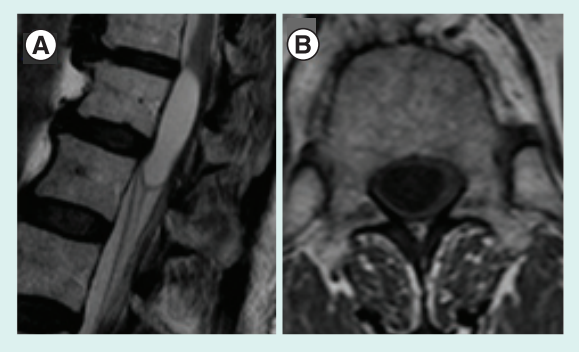

图1所示。T2矢状位(A)和T1轴位(B)示圆锥中心的囊性病变,T1低信号,T2高信号。由于患者拒绝注射造影剂,无法获得增强图像

胸腰椎MRI显示以锥形为中心的囊性病变(图1)。由于患者拒绝进行造影,未给予造影。1例McCormick II级肿瘤入院。行后路背侧入路。行D10 D11椎板切除术,后正中切口切开硬脑膜。病变经超声支持确诊。它的左边有一个卵裂平面,但在它的右边神经实质是难以区分的。完成了部分切除和与蛛网膜下腔的程度的通信。